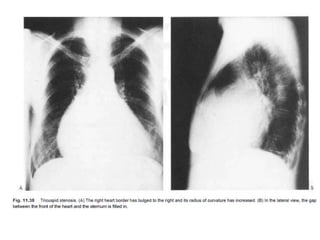

• Important tricuspid valve disease will cause

enlargement of the right atrium, producing a

prominent, bulging or elongated right heart border

• This appearance has a single margin and is distinct

from the 'double heart border' produced by left atrial

enlargement.

• The difference can be distinguished by the position of

entry of the IVC, this structure limiting the expansion

of the right atrium. Significant cardiomegaly can be

caused by right atrial enlargement